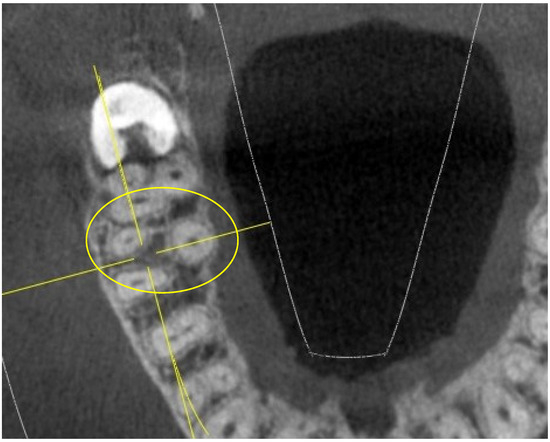

Upper First and Second Molar Pulp Chamber Endodontic Anatomy Evaluation According to a Recent Classification: A Cone Beam Computed Tomography Study

2. Materials and Methods

- long and short diameter of the pulp chamber floor;

- shape of the pulp chamber associated with a letter of the alphabet (in relation to the number and arrangement of canal orifices);

- diameter of root canal orifices;

- distance between intra- and inter-root canals;

- possible fusion of the roots;

- root diameter.